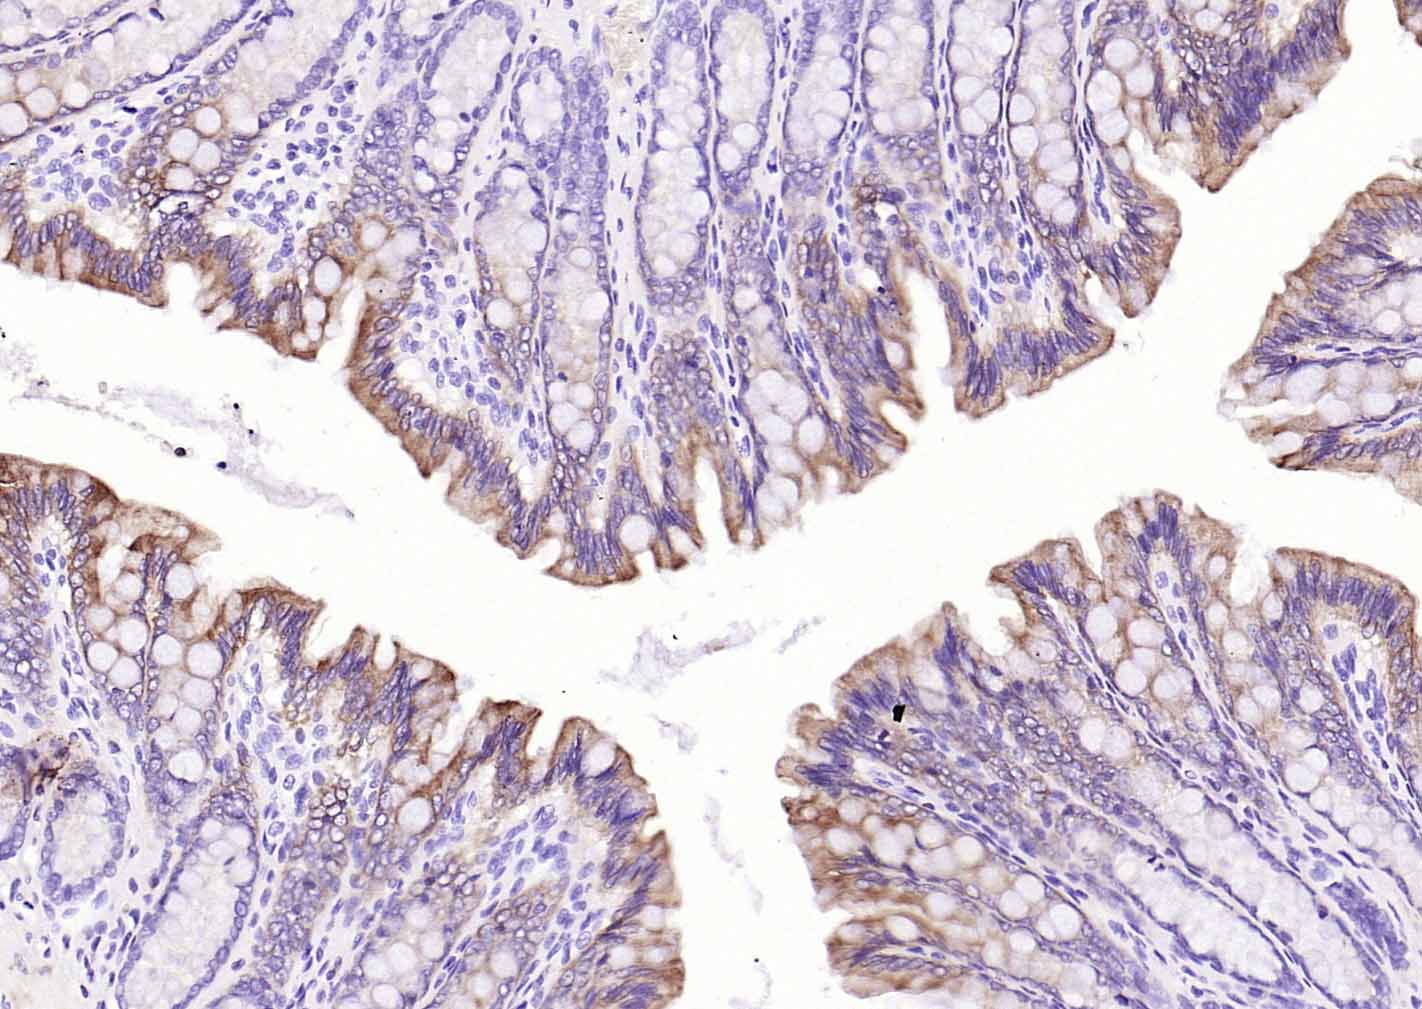

P-CK广谱细胞角蛋白(AE1/AE3)主要标记角化上皮、复层鳞状上皮、复层上皮、增生的角化上皮和单层上皮,用于鳞癌,各种腺癌 、移行上皮癌,小细胞癌,恶性间皮瘤、生殖细胞肿瘤,部分滑膜肉瘤、平滑肌肉瘤等表达。

广谱细胞角蛋白PCK单克隆抗体-bsm-34137M广谱细胞角蛋白PCK单克隆抗体-bsm-34137M广谱细胞角蛋白PCK单克隆抗体-bsm-34137M广谱细胞角蛋白PCK单克隆抗体-bsm-34137M广谱细胞角蛋白PCK单克隆抗体-bsm-34137M广谱细胞角蛋白PCK单克隆抗体-bsm-34137M广谱细胞角蛋白PCK单克隆抗体-bsm-34137M广谱细胞角蛋白PCK单克隆抗体-bsm-34137M广谱细胞角蛋白PCK单克隆抗体-bsm-34137M广谱细胞角蛋白PCK单克隆抗体-bsm-34137M广谱细胞角蛋白PCK单克隆抗体-bsm-34137M广谱细胞角蛋白PCK单克隆抗体-bsm-34137M广谱细胞角蛋白PCK单克隆抗体-bsm-34137M广谱细胞角蛋白PCK单克隆抗体-bsm-34137M广谱细胞角蛋白PCK单克隆抗体-bsm-34137M

IHC-PHuman, Mouse, Rat1:100-500